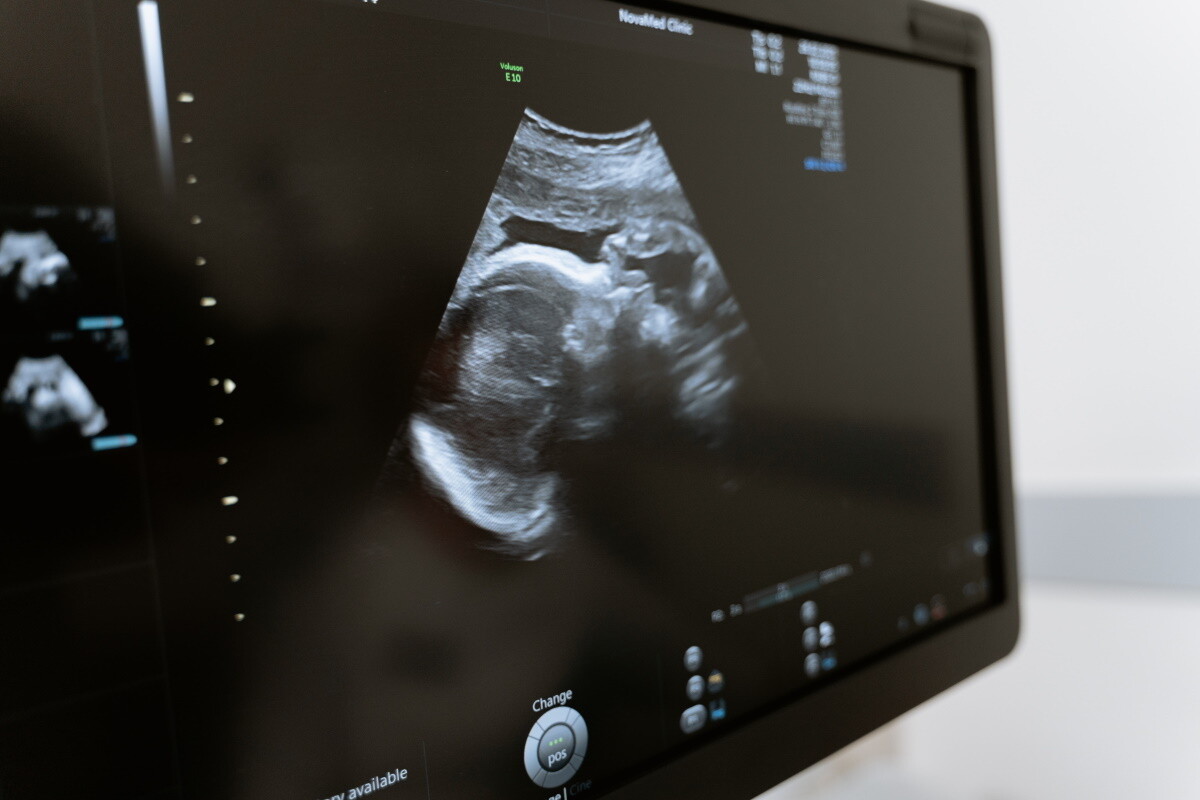

Фото: pexels